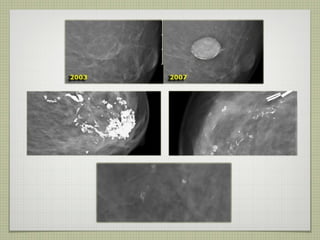

la ausencia de cambios en el  intervalo de microcalcificaciones  probablemente benignas sobre  la base de criterios morfológicos  es una señal alentadora y una  indicación para la continuación de  mamografías de seguimiento. Por otra parte en un estudio retrospectivo que incluyó a grupos indeterminados y sospechoso de microcalcificaciones, la estabilidad no puede ser tomada como un signo alentador de benignidad. En este grupo de pacientes con neoplasia, el 25% de los pacientes tenía microcalcificaciones estable durante 8-63. la morfología de las calcificaciones es mucho más importante que la estabilidad y sólo puede ser invocada si las calcificaciones tienen una forma probablemente benignas.

la ausencia decambios en el intervalo de microcalcificaciones probablemente benignas sobre la base de criterios morfológicos es una señal alentadora y una indicación para la continuación de mamografías de seguimiento. Por otra parte en un estudio retrospectivo que incluyó a grupos indeterminados y sospechoso de microcalcificaciones, la estabilidad no puede ser tomada como un signo alentador de benignidad. En este grupo de pacientes con neoplasia, el 25% de los pacientes tenía microcalcificaciones estable durante 8-63. la morfología de las calcificaciones es mucho más importante que la estabilidad y sólo puede ser invocada si las calcificaciones tienen una forma probablemente benignas.